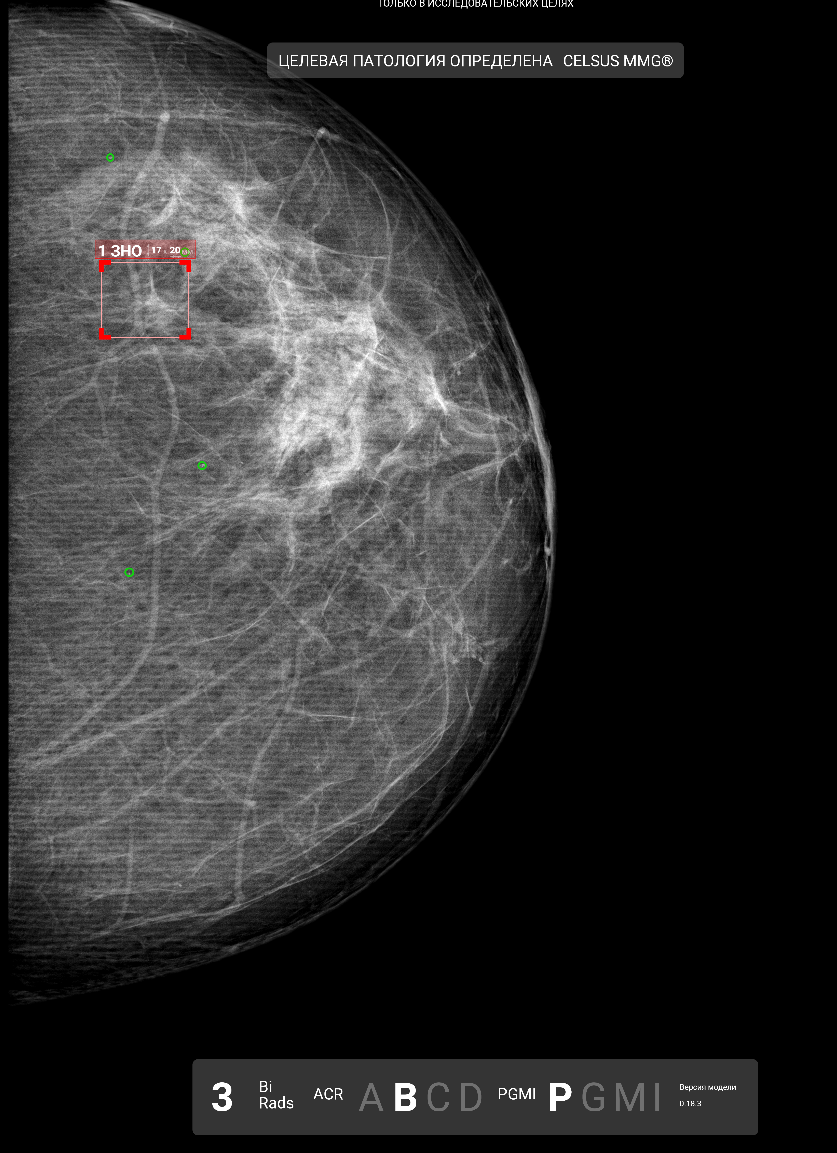

Highly Sensitive AI Will Reduce the Need for Human Image Interpretation

Идея этого сценария работы проста - часть исследований может обрабатываться автоматически, без какого-либо участия врача. Особенно это актуально для сценариев массового скрининга, где подавляющее количество исследований не содержит патологию и не представляет большой сложности в плане интерпретации.

По итогам 3 квартала этого года наш сервис по флюорографии обработал в сценарии "highly sensitive AI" более 60к исследований. Чувствительность сервиса составила 99.93% при автоматической генерации заключения "без патологии" для 67% исследований. При этом пересмотр врача-эксперта подтвердил расхождение только для 40% из этих 0.07% расхождений. Иными словами, сервис автоматически присвоил категорию "норма" более 40к исследованиям, при этом было допущено около 15-20 ошибок.

Барьеров для полноценного внедрения ещё немало - нужно ещё сильнее улучшать чувствительность (в основном решать проблемы со всякими сложными случаями и редкими патологиями) и понять, что делать с точки зрения ответственности разработчиков в случае ошибки, но перспективы реального применения автономных сценариев явно вышли из области фантастики.